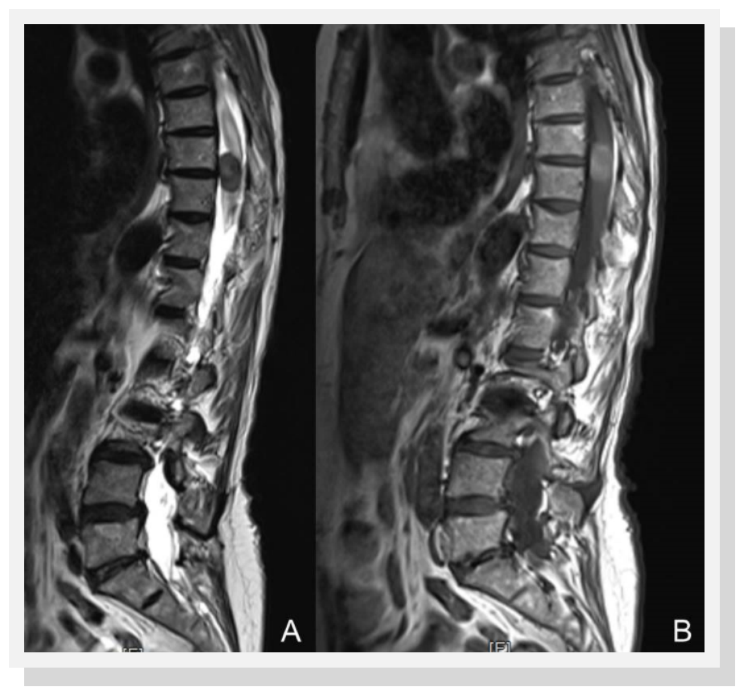

A 74-year-old woman presented complaining a several-month history of increasing thoracic back pain and left leg pain. Neurological examination demonstrated a spastic paraparetic gait and hyperreflexia of the lower limbs. Spinal magnetic resonance imaging revealed an intramedullary mass extending from T7 to T11 measuring 22 x 12 x 15 mm, slightly hyperintense on T1weighted images and hypointense on T2 weighted sequences and showed mild and heterogeneous enhancement after injection of gadolinium (Figure 1). Motor and somatosensory evoked potentials (SSEP) were recorded during surgery. A T7-T11 laminectomy and posterior midline myelotomy was performed. The exposed black and rigid tissue was removed en block (Figure 2). Gross total removal was achieved, as confirmed by MRI with and without contrast 24 hours after operation.

Figure 1.Spinal magnetic resonance imaging showing an intramedullary mass extending from T7-11 A) hypointense on T2 weighted sequences and B) slightly hyperintense on T1weighted imagines with mild and heterogeneous enhancement after the injection of gadolinium.

Typical MRI show an intramedullary lesion that appears isointense on T1-weighted sequences, hypointense on T2 weighted sequences, and enhances homogenously with gadolinium. These signal features are inconsistent due to the variable degree of tumour melanisation, which affects the signal characteristics on MRI. Hence, meningeal melanocytoma should be included in the differential diagnosis of lesions as ependymoma, meningioma and intramedullary astrocytoma 5, 6, 7.